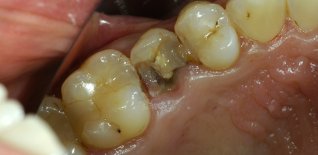

Frattura del secondo premolare superiore.